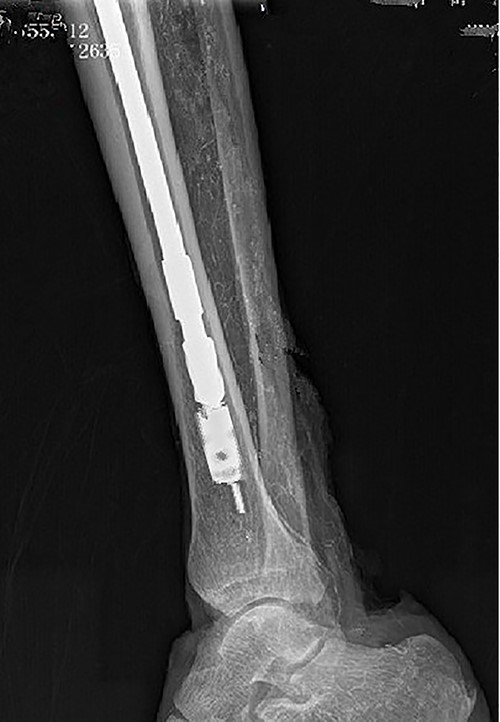

Intraoperative X-ray showing that the broken nail extractor was inserted into the medullary cavity and passed through the canal of the broken nail.